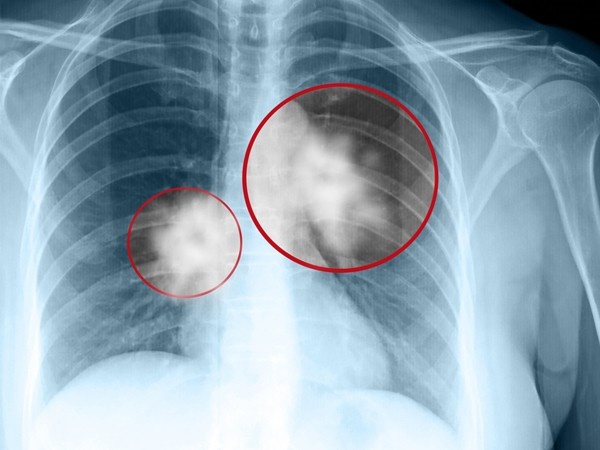

| Bệnh ung thư phổi là nguyên nhân hàng đầu gây tử vong do ung thư ở nam giới. Ảnh: Onmed.gr. |

Dựa vào đặc điểm mô bệnh học, Tổ chức Y tế thế giới (WHO) chia ung thư phổi thành 2 loại chính: ung thư phổi không tế bào nhỏ (Non-Small Cell Lung Cancer) và ung thư phổi tế bào nhỏ (Small Cell Lung Cancer). Trong đó, ung thư phổi không tế bào nhỏ chiếm khoảng 85% các ca.

Khoảng 30% bệnh nhân ung thư phổi không tế bào nhỏ được chẩn đoán ở giai đoạn sớm (giai đoạn 1,2). 70% bệnh nhân được chẩn đoán ở giai đoạn muộn (giai đoạn 3,4). Vì thế, dù có nhiều bước tiến trong chẩn đoán và điều trị, ung thư phổi vẫn thường có tiên lượng xấu và tỷ lệ sống thêm 5 năm khá thấp.

Tại Việt Nam, đa phần bệnh nhân được phát hiện khi đã ở giai đoạn muộn, chỉ 10-20% được chẩn đoán ở giai đoạn sớm. Theo TS Chân ở giai đoạn sớm bệnh có những triệu chứng rất nghèo nàn, bệnh nhân dễ nhầm lẫn với những bệnh lý về đường hô hấp khác.

Theo TS Chân, rất nhiều bệnh nhân ung thư phổi không hề có triệu chứng ở giai đoạn đầu, đến khi xuất hiện dấu hiệu như ho, đau ngực, khó thở, gầy sút cân,... họ mới đi khám. Khi đó, hầu hết trường hợp bệnh đều đã ở giai đoạn muộn, không thể chỉ định phẫu thuật. Thời gian sống sau khi được phát hiện rất ngắn.